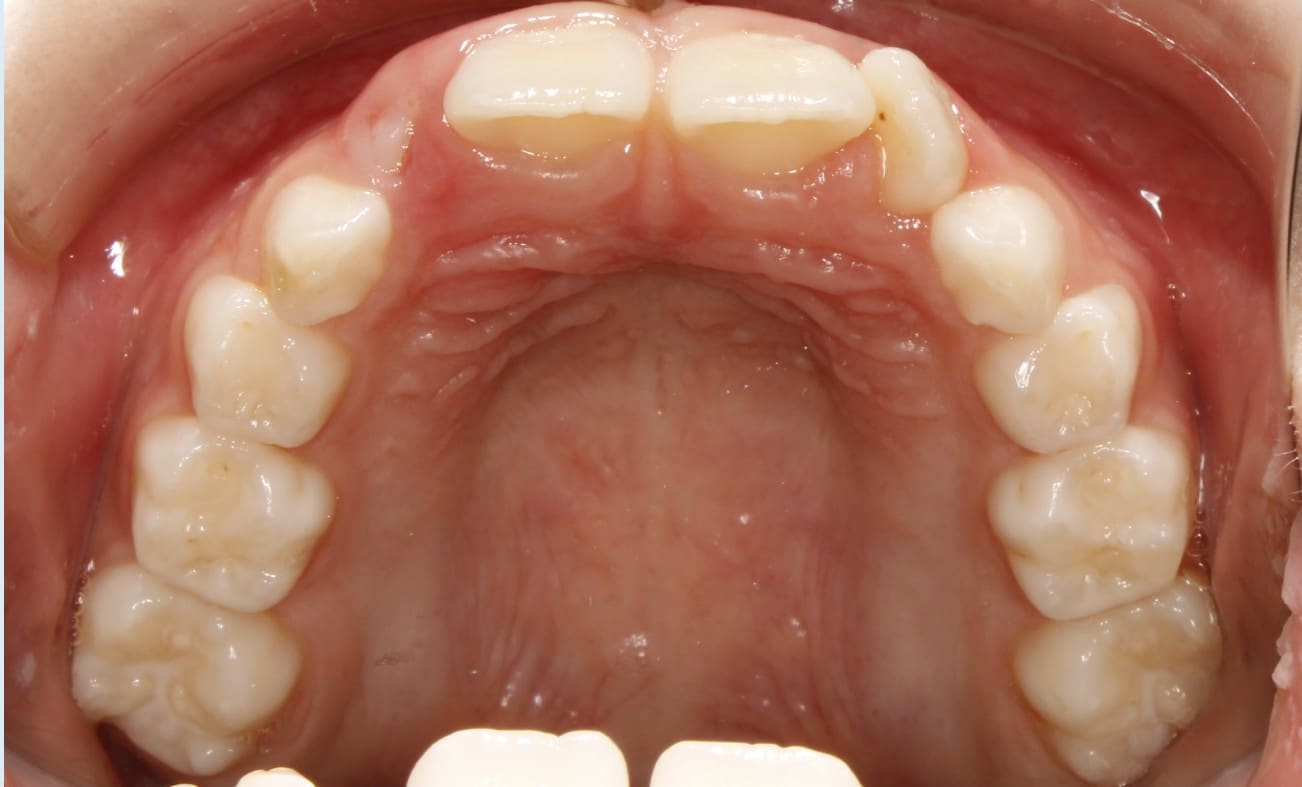

Phase I treatment with an Expander and Invisalign aligners

Phase I treatment with an Expander and Invisalign aligners to create space for permanent teethÂ